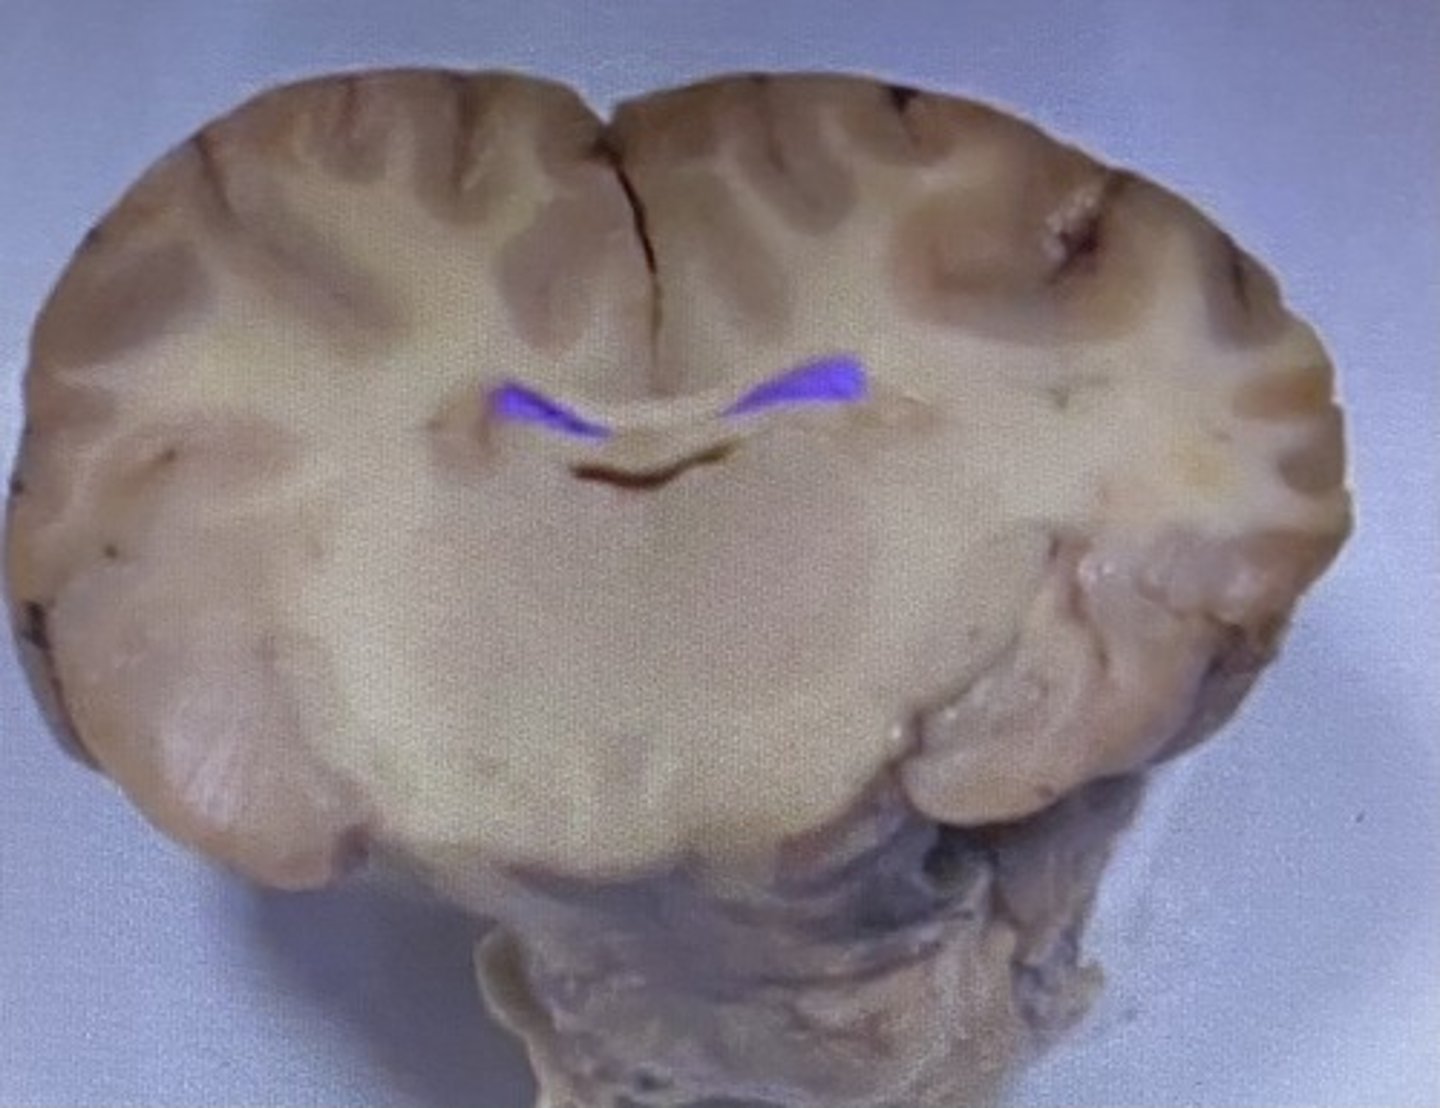

Sheep Lateral Ventricle

-produces and contains cerebrospinal fluid

Fornix

Lateral Ventricle